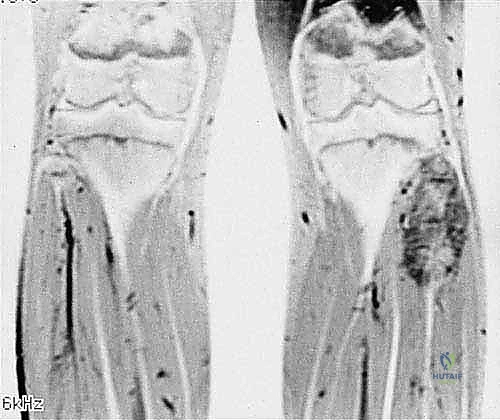

- التصوير بالرنين المغناطيسي (MRI): المعيار الذهبي. يوضح بدقة متناهية امتداد الورم داخل نخاع العظم، وحجم الكتلة في الأنسجة الرخوة المحيطة، وعلاقة الورم بالأعصاب والأوعية الدموية.

- المسح الذري للعظام (Bone Scan) أو التصوير البوزيتروني (PET Scan): للتحقق مما إذا كان الورم قد انتشر إلى عظام أخرى في الجسم.

* الساركوما العظمية (Osteosarcoma): الورم الخبيث الأكثر شيوعاً في العظام، وغالباً ما يصيب الأطفال والشباب. يتميز بنمو سريع وتدمير للعظم.

* ساركوما إيوينغ (Ewing Sarcoma): يصيب عادة الأطفال والمراهقين، وينشأ في تجويف النخاع العظمي للشظية.

* الساركوما الغضروفية (Chondrosarcoma): ينشأ من الخلايا الغضروفية، ويصيب عادة البالغين وكبار السن.

3. الأورام النقيلية (Metastatic Bone Tumors)

في بعض الأحيان، تنتشر السرطانات من أعضاء أخرى (مثل الثدي، الرئة، البروستاتا، أو الكلى) وتستقر في عظم الشظية مسببة ألماً شديداً وكسوراً مرضية.